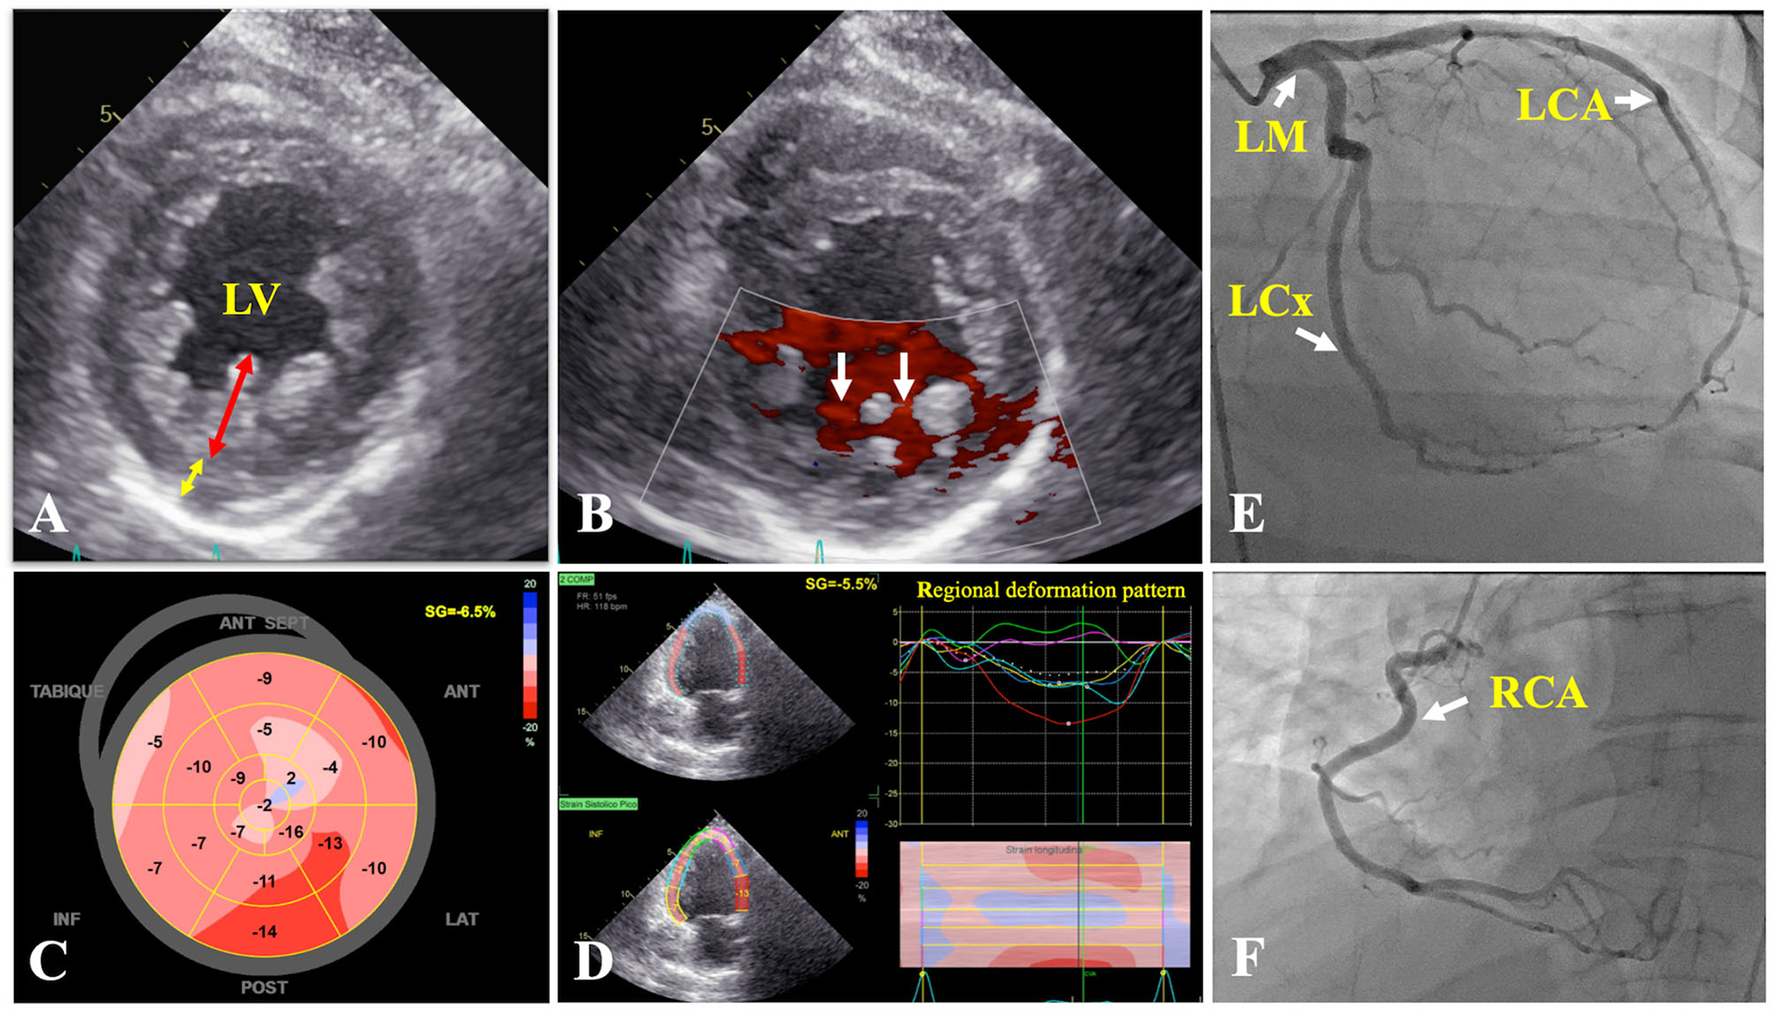

Transthoracic echocardiogram (TTE) demonstrated a left ventricular ejection fraction (LVEF) of 30%, mildly dilated, diffusely hypokinetic, prominent trabeculations of LV, and a non-compacted to compacted (NC/C) myocardium ratio of 2.75 in end-systole at inferolateral mid-ventricular level (Figures 2A–D), so the diagnosis of NCCM was realized. On the sixth hospital day, coronary angiography revealed that coronary arteries were normal (Figures 2E,F). Right-sided cardiac catheterization showed normal cardiac index and absence of pulmonary hypertension.

Figure 2

Transthoracic echocardiogram. (A) Parasternal short axis of the mid left ventricle demonstrating two-layer myocardial structure, with a ratio of ticker non-compacted (redline) to thin compacted (yellow line) myocardium >2 at end-systole in the inferolateral segment. (B) Flow between intertrabecular recesses by intraventricular blood on color Doppler (white arrows). (C) Reduced global longitudinal strain (−6.5%). (D) Two-chamber view showing a regional deformation pattern with a markedly decreased myocardial deformation in apical segments (green and purple curves) in comparison to basal segments (red and yellow curves). Coronary angiography: coronary arteries without lesions (E,F) (white arrows). LCA, left coronary artery; LCx, left circumflex coronary artery; LM, left main coronary artery; LV, left ventricle; RCA, right coronary artery.

The TTE fulfills a fundamental value in the initial diagnostic approach, being Jenni's criteria the most widely used, and evaluates a two-layer ventricular myocardium with thick non-compacted and thinner compacted myocardium, generating an NC/C ratio >2 in end-systole on short-axis parasternal view (11). These alterations affect predominantly the mid-lateral, mid-inferior, mid-anterior, and apical LV areas (12). Finally, prominent excessive trabeculations and the flow between the deep intertrabecular recesses by color Doppler and excluded coexisting structural cardiac abnormalities are also considered (11). Cardiac magnetic resonance (CMR) allows us to confirm the diagnosis with 86% sensitivity and 99% specificity, following Petersen's criteria that consider an NC/C ratio >2.3 in end-diastole (11). Both criteria were met by our patient. The differential diagnosis by TTE was made with a normal variation of myocardial trabeculations, defined as less than 3 trabeculations located in the LV apex, also with LV apical thrombi, false tendons, aberrant chords, cardiac tumors, hypertrophic cardiomyopathy (HCM), and dilated cardiomyopathy (DCM) (12, 13). The LV apical thrombi are distinguished by their higher echogenicity compared to myocardium; false tendons and aberrant cords usually cross the LV cavity (13). None of these findings were observed in our patient, neither was any cardiac tumor. Recently, the characteristics of Speckle Tracking in NCCM began to be studied, evidencing a reduced global longitudinal strain, with greater involvement of the apical segments, generating a significant basal-to-apical gradient, useful to differentiate it from HCM and DCM (11, 13). Additionally, it differs from HCM, since trabeculations and crypts that can mimic NCCM are mainly limited to the basal ventricular septum or the posterior wall (13).